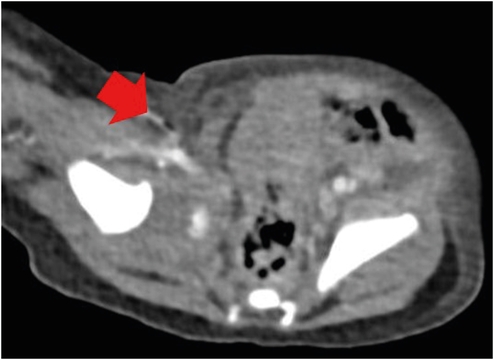

Laboratory tests at the ER indicated leukopenia (white blood cell count, 1,760/μL; neutrophil, 41%; absolute neutrophil count, 720/μL). Consequently, subcutaneous administration of granulocyte colony-stimulating factor (10 mcg/kg) was initiated, along with the administration of broad-spectrum empirical antibiotics. Ultrasonography demonstrated air bubbles in the subcutaneous layer of the discolored mons pubis and inguinal areas. The skin discoloration rapidly extended to labia majora, abdominal wall and flank area. Fig. 1 illustrates the rapid progression of the skin lesion in several hours. A computed tomography (CT) scan was performed to determine the extent of necrotizing fasciitis. There were air bubbles in the subcutaneous tissue and fascia of the right groin and proximal thigh on the CT scan (Fig. 2). Based on the clinical features and radiologic findings, she was diagnosed with Fournier’s gangrene, and an emergency operation was scheduled. The patient was placed in a supine position under general anesthesia. A low transverse incision was made at mons pubis to open subcutaneous tissue from skin to fascia (Fig. 3). The tissue at the subcutaneous and the fascia layer was vulnerable, with evident exudates, and necrosis was advancing. Curettage was performed to remove necrotic tissue, followed by irrigation using a solution of betadine diluted with saline. Subsequently, the wound was covered with a dressing soaked in betadine; and it was left open and not sutured.

Fig. 2

Abdominal computed tomography; air bubbles in the subcutaneous tissue of the right groin and proximal inner thigh (arrow).